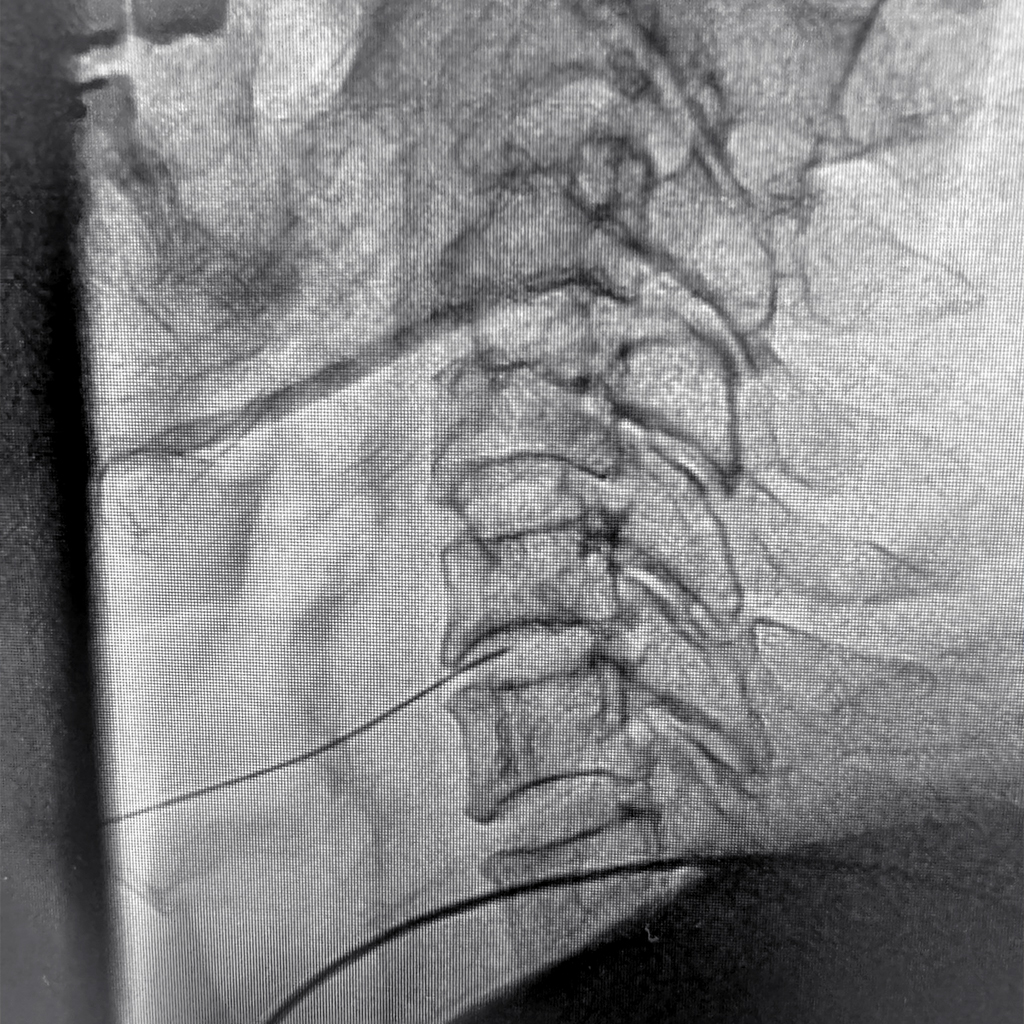

レントゲン透視画像

椎間板に穿刺針を挿入したところです。Annulogram検査を行った後、ディスクシール治療を行います。腰椎治療と比較して難易度は低いです。頸椎のPLDDも同様ですが、穿刺針が太くなる分だけ注意が必要になると思います。